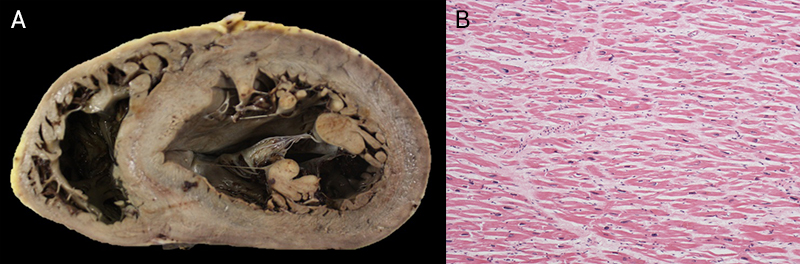

Hypertrophic cardiomyopathy (HCM) is cardiologically defined as a left ventricular wall thickness of 15 mm or more in any myocardial segment that is not explained solely by loading conditions. The disease is estimated to have a prevalence of one in 500 in the general population.23 HCM is reported to cause between 2% and 36% of SCD in athletes,5,16,24 and is reported as the most common cause of SCD in athletes in the US, making up 36%.16 Contrastingly, in the UK, HCM causes 6% of SCDs.5 Most HCM patients die suddenly at rest, rather than on exertion.25,26 The differences in the proportion of SCD caused by HCM in all these studies may be explained by how the diagnosis is made.4 At autopsy, on macroscopic examination there is frequently increased heart weight with asymmetric left ventricular hypertrophy27 (figure 1A) and normal coronary arteries. It is important to state that the heart can appear normal in 30% of cases, so pathologists need to be aware that histology should be taken on all normal hearts in individuals with SCD.25

The diagnosis is made histologically with the detection of widespread myocyte disarray in the left ventricle (figure 1B). Pathologists need to be strict in their definition of myocyte disarray and guidelines should be carefully followed.19 There is a genetic cause in up to 70% of cases. Once the diagnosis is made, then the pathologist informs the medical examiner and coroner who will inform the family that they need cardiological screening in view of the SCD. Sudden death is the first presentation with the diagnosis made at autopsy in 79% of cases in our HCM series, emphasising the role of the autopsy and pathologist.25,28